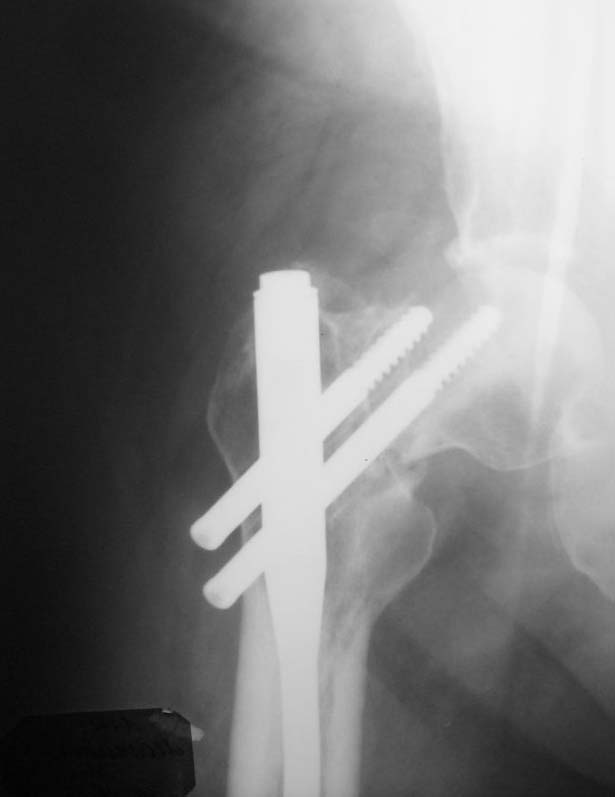

Пациент (мужчина), 34 года. Травма в результате ДТП в апреле 2011 года. Проводилось оперативное лечение – закрытая репозиция, остеосинтез AFN. В октябре 2011 года – декортикация, тунелизация, фиксация отломков верхней трети диафиза бедренной кости проволочным серкляжом, удаление дистального блокирующего винта. На контрольных рентгенограммах определяется миграция шеечных винтов конструкции. Пациент передвигается на костылях с дозированной нагрузкой на ногу (полная нагрузка болезненна в области тазобедренного сустава). Вариант лечения - тотальное эндопротезирование тазобедренного сустава+остеосинтез верхней трети диафиза бедренной кости (ретроградным стержнем ЦИТО, пластиной, АНФ).Жду Ваших комментариев

Добрый день! Думаю, что все предшествующие проблемы из-за некорректной установки данной металлоконструкции. Не надо было добиваться красивой рентгенкартинки используя серкляжи и т.п.. Устранены все виды смещения - этого уже достаточно (один из основных принципов БИОСА сохранение перирефрактурной гематомы, нарушив периоссальную васкуляризацию с интрамедуллярной- получили замедленную консолидацию). К сожалению шеечные винты даже с поправкой на их миграцию тоже утановлены не совсем корректно. Но это по большому счёту бывает у каждого, кто хорошо работает, ошибок нет если ничего не делать. В данной ситуации ставить протез на длинной ножке, убирая из фнкции половину нормальной бедренной кости у молодого 34-х летнего человека считаю абсолютно нецелесообразным. Конечно полной информацией о данном больном не владею, но думаю, что на данном этапе только реостеосинтез, Любой длинный проксимальный вертельный стержень, большего диаметра (Де-пьюшный Афиксус, страйкеровскую Гамму и т.д., принципиального значения не имеет, что возможно в Ваших условиях), с рассверливанием интрамедуллярного канала и корректной установкой шеечных винтов, с выведением нормального шеечно-диафизарного угла и умеренной компрессией на шеечном винте шейки бедренной кости. Установку провести в динамическом варианте и дозированную нагрузку сразу. Думаю проблему с диафизом Вы решите, что касается шейки-решать по мере поступления, если встанет вопрос через некоторое время об энопротезировании, то это будет классический тотальник, без удлинённых ножек, с типичной техникой операции эндопротезирования, что думаю важно для 34-х лет.

Головка вроде еще живая, думаю стоит побороться за сустав. Подвертельная корригирующая остеотомия короткой гаммой или отмоделировать LCP с 2 винтами в шейку. На диафиз LCP MIPO или ретроградный штифт с блокированием.